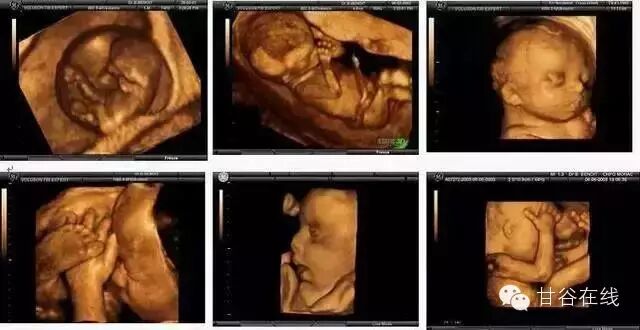

四维彩超就是四维成像技术(4D),能直观,立体显示人体器官的三维结构及动态、实时地观察立体结构。主要可以进行胎龄检测、分析胎儿的发育情况、筛查胎儿畸形等。

单胎为怀孕第20—28周,双胞胎为18-22周。因为这个时期的胎儿大小适中,羊水量充足,比较容易采集到相对清晰的图像。

四维彩超动图欣赏

揉眼睛

麻麻,我在挠耳朵

嚯嚯~打拳啦!